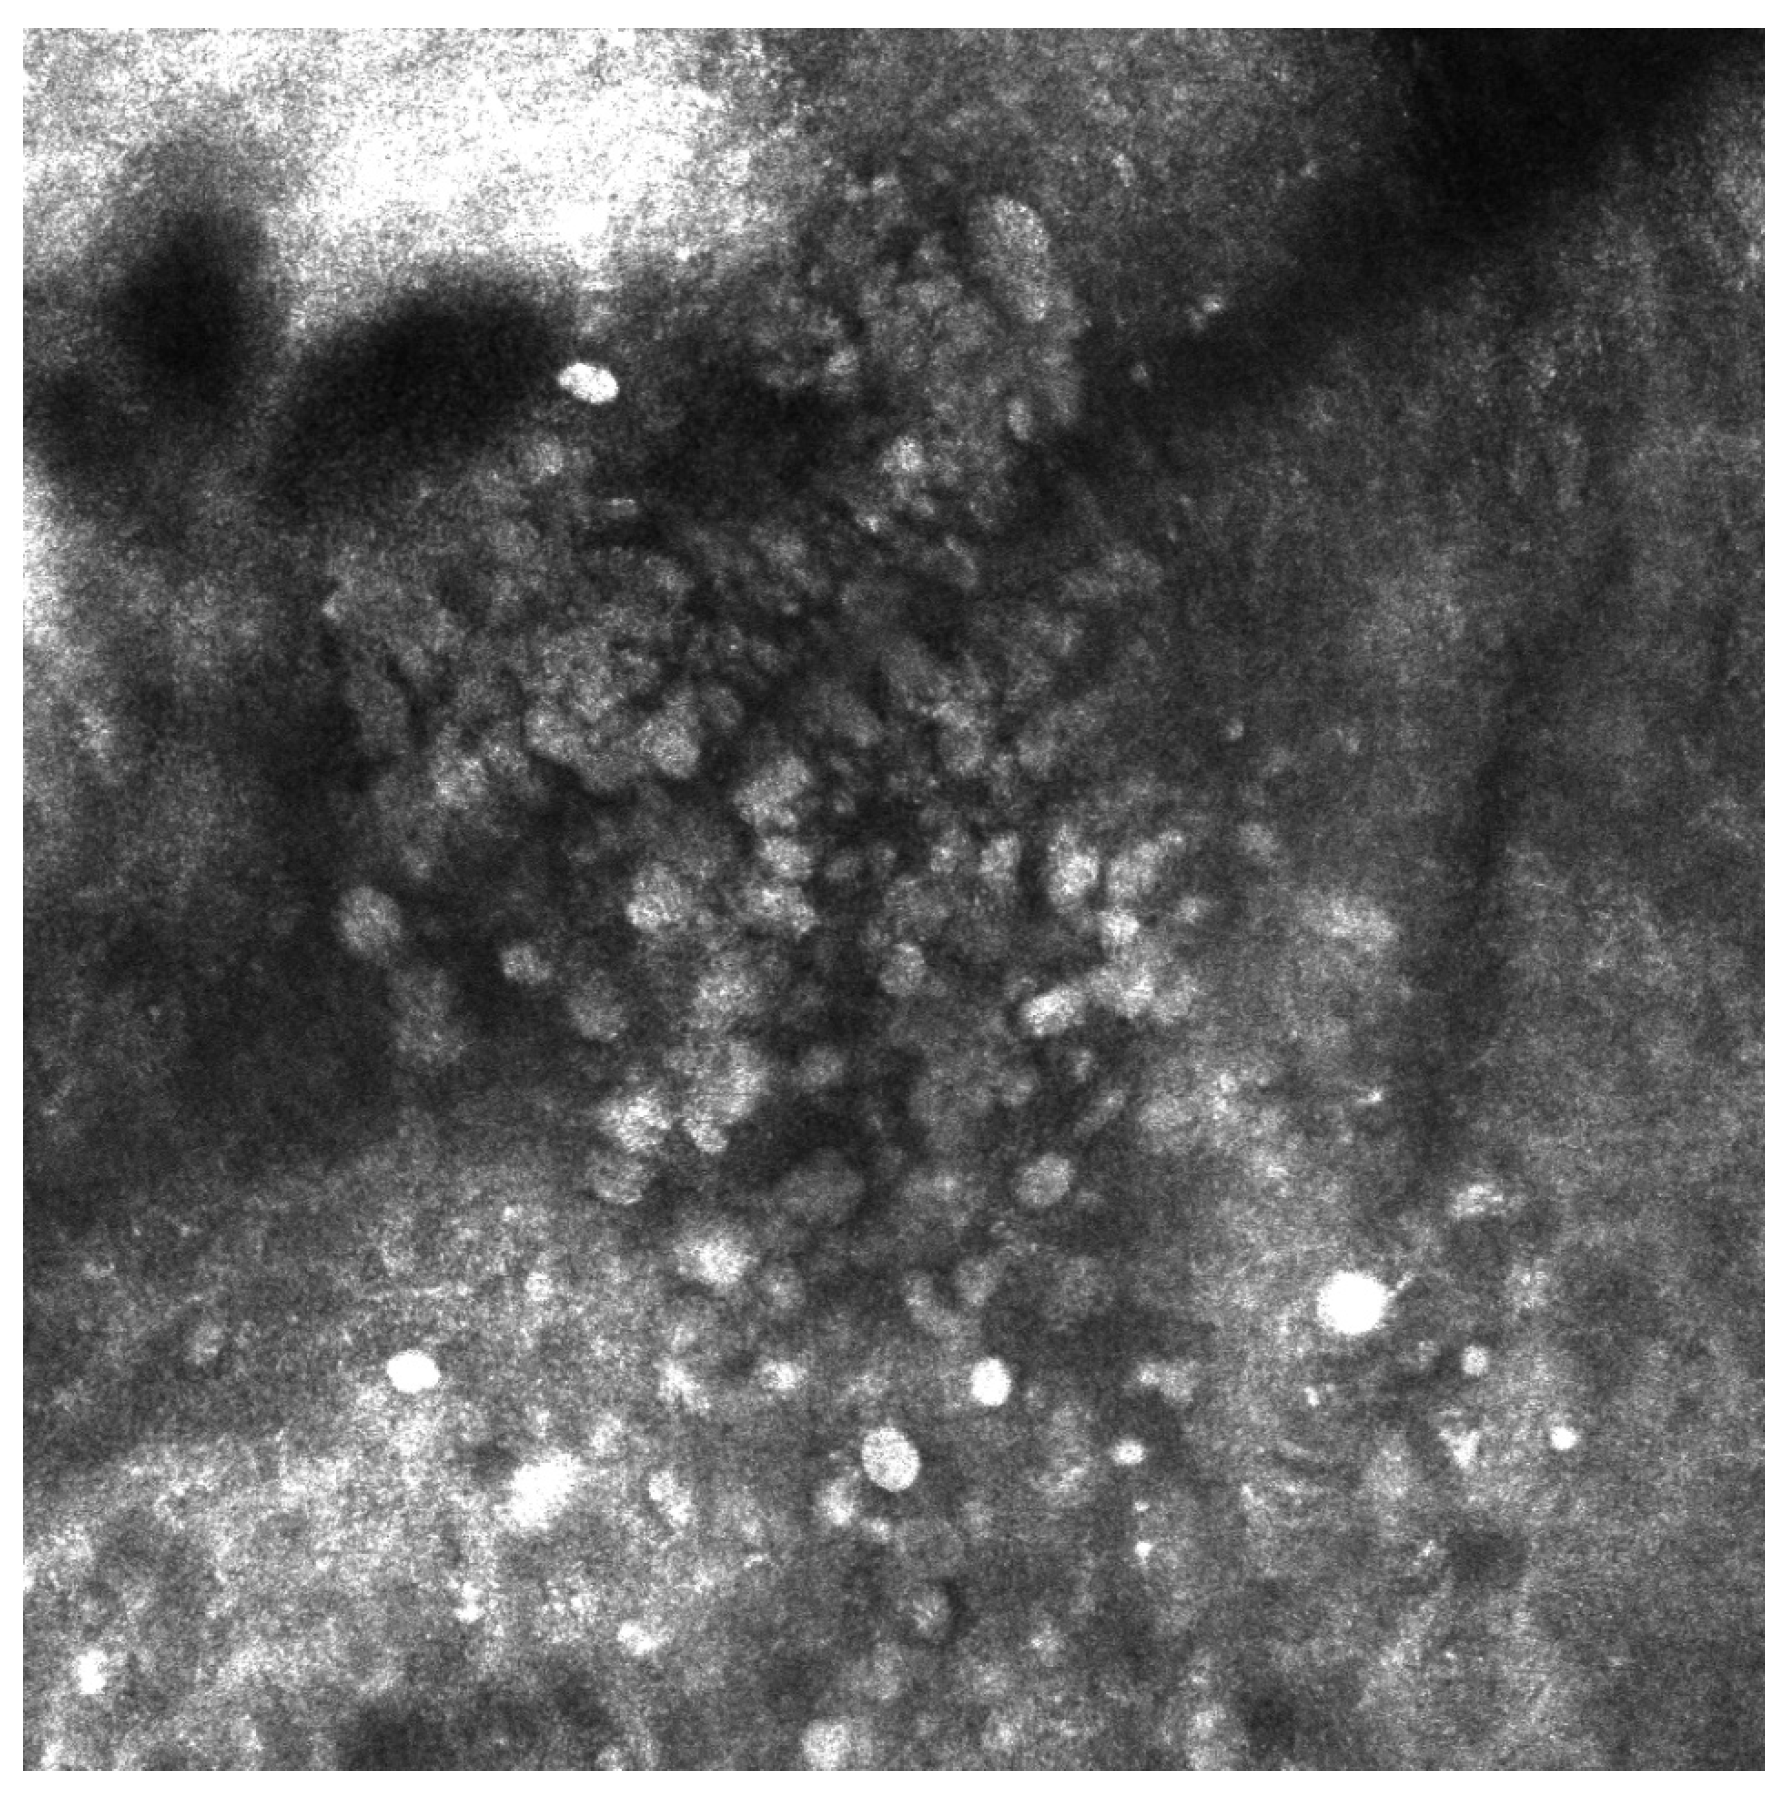

- Del Río-Sancho, S.; Gallay, C.; Ventéjou, S.; Christen-Zaech, S. Non-invasive imaging of agminated Spitz nevi with line-field confocal optical coherence tomography. J. Eur. Acad. Dermatol. Venereol. 2023, 37, e658–e659. [Google Scholar] [CrossRef]